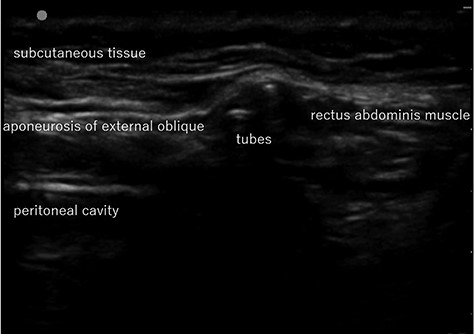

Abdominal US image in Case 1: US showed the tubes running under the aponeurosis of the external oblique that is the anterior wall of the inguinal canal.

computed tomography (CT) showed right IH and a balloon that was placed by the bladder and a connecting catheter that went through the lateral side of the rectus abdominis muscle (Fig. 2). In the operation, we performed ultrasonography (US) at first and it demonstrated that the catheter was running through the inguinal canal (Fig. 3). When we incised the aponeurosis of the external abdominal oblique muscle, the catheter of the AUS was observed in the inguinal canal (Fig. 4). We identified the hernia sac protruding from the inguinal ring and diagnosed it as an indirect IH. The adhesion was too hard to separate the catheter from the pubis and posterior wall of the inguinal canal around pubis. Then, the IH was repaired using the Lichtenstein technique; however, the mesh near the pubis could not be spread as ordinarily.